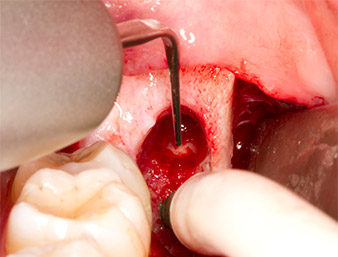

The tissue above the root remnant was not completely ossified and consisted for the most part of granulation tissue modified by inflammation (Fig. 4).

To obtain autogenous material for subsequent wound treatment, healthy bone chips were harvested from the surroundings of the root remnant with a piezo surgical instrument (Piezomed B5) (Fig. 5).

The autogenous tissue was removed with the scraper-shaped section of the working part of the instrument and stored in a physiological saline solution until further use (cf. Fig. 13).